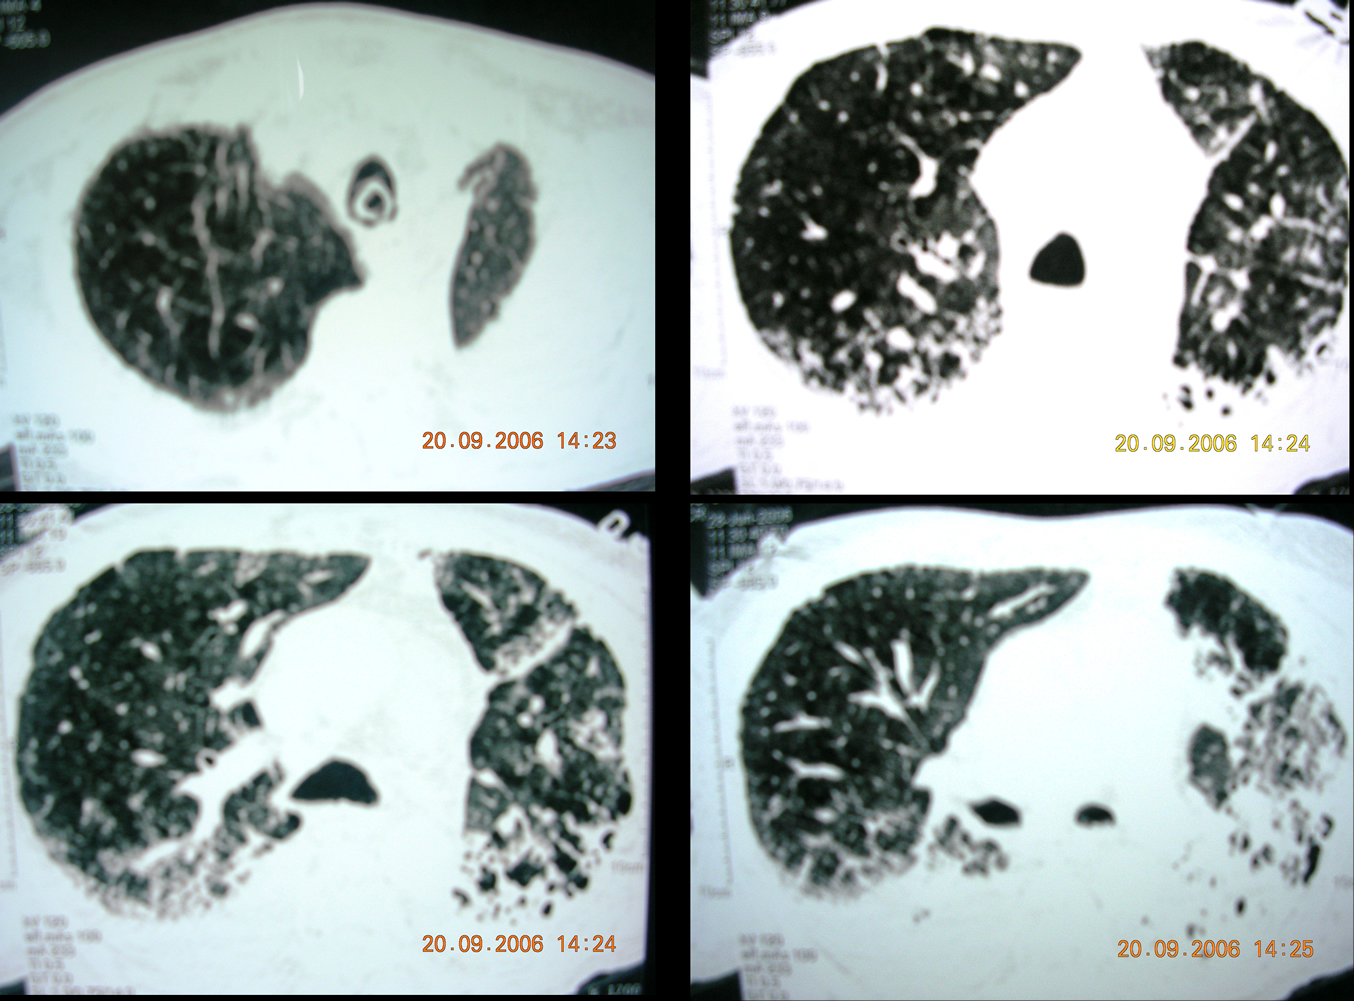

- Chest Spiral CT with PE protocol (Fig 2): patchy consolidations with increased interstitial markings and alveolar filling, no filling defects in the pulmonary arteries